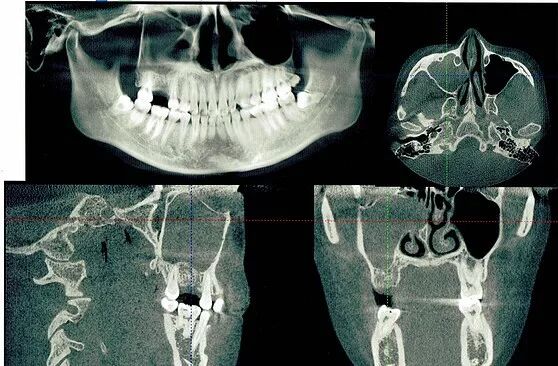

我是过敏性鼻炎患者,由于拍摄牙齿3维X光,发现上额窦出现堵塞,赶紧去综合性医院进行鼻子检查,我一直早上起来的第一件事就是打喷嚏 ,终于找到原因了。2013年被诊断为慢性化脓性鼻窦炎、鼻中隔偏曲、过敏性鼻炎,进行了全麻鼻中隔矫正术,鼻窦开放术,双侧下鼻甲等离子消融术,

右侧上额窦出现囊肿,正常情况下应该是透明,由于直接连着我需要做种植牙的位置,所以需要首先做鼻窦手术,然后才能做牙齿手术,我的人生还是一波又一波 。

二期手术前,医生还是需要拍X光了解种植体情况。真是不知道拍了多少X光。。。